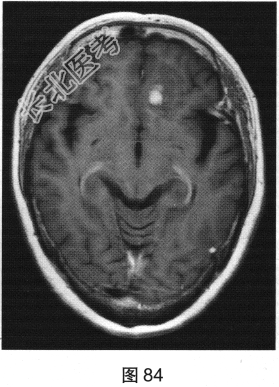

- 多项选择题2.[提示]患者行MRI检查,如图80~图85所示。患者MRI检查的阳性影像学表现包括( )

B、病变增强扫描未见明显强化

D、FLAIR呈稍高信号

E、病变增强扫描可见明显强化

G、MRI示左侧异常信号影

H、MRI示右侧异常信号影

- 多项选择题3.根据患者病史及影像学检查,提示其可能的诊断是( )

A、肉芽肿

B、特发性肥厚性硬脑膜炎

C、脑膜瘤

D、低级别星形细胞瘤

E、淋巴瘤

F、转移瘤